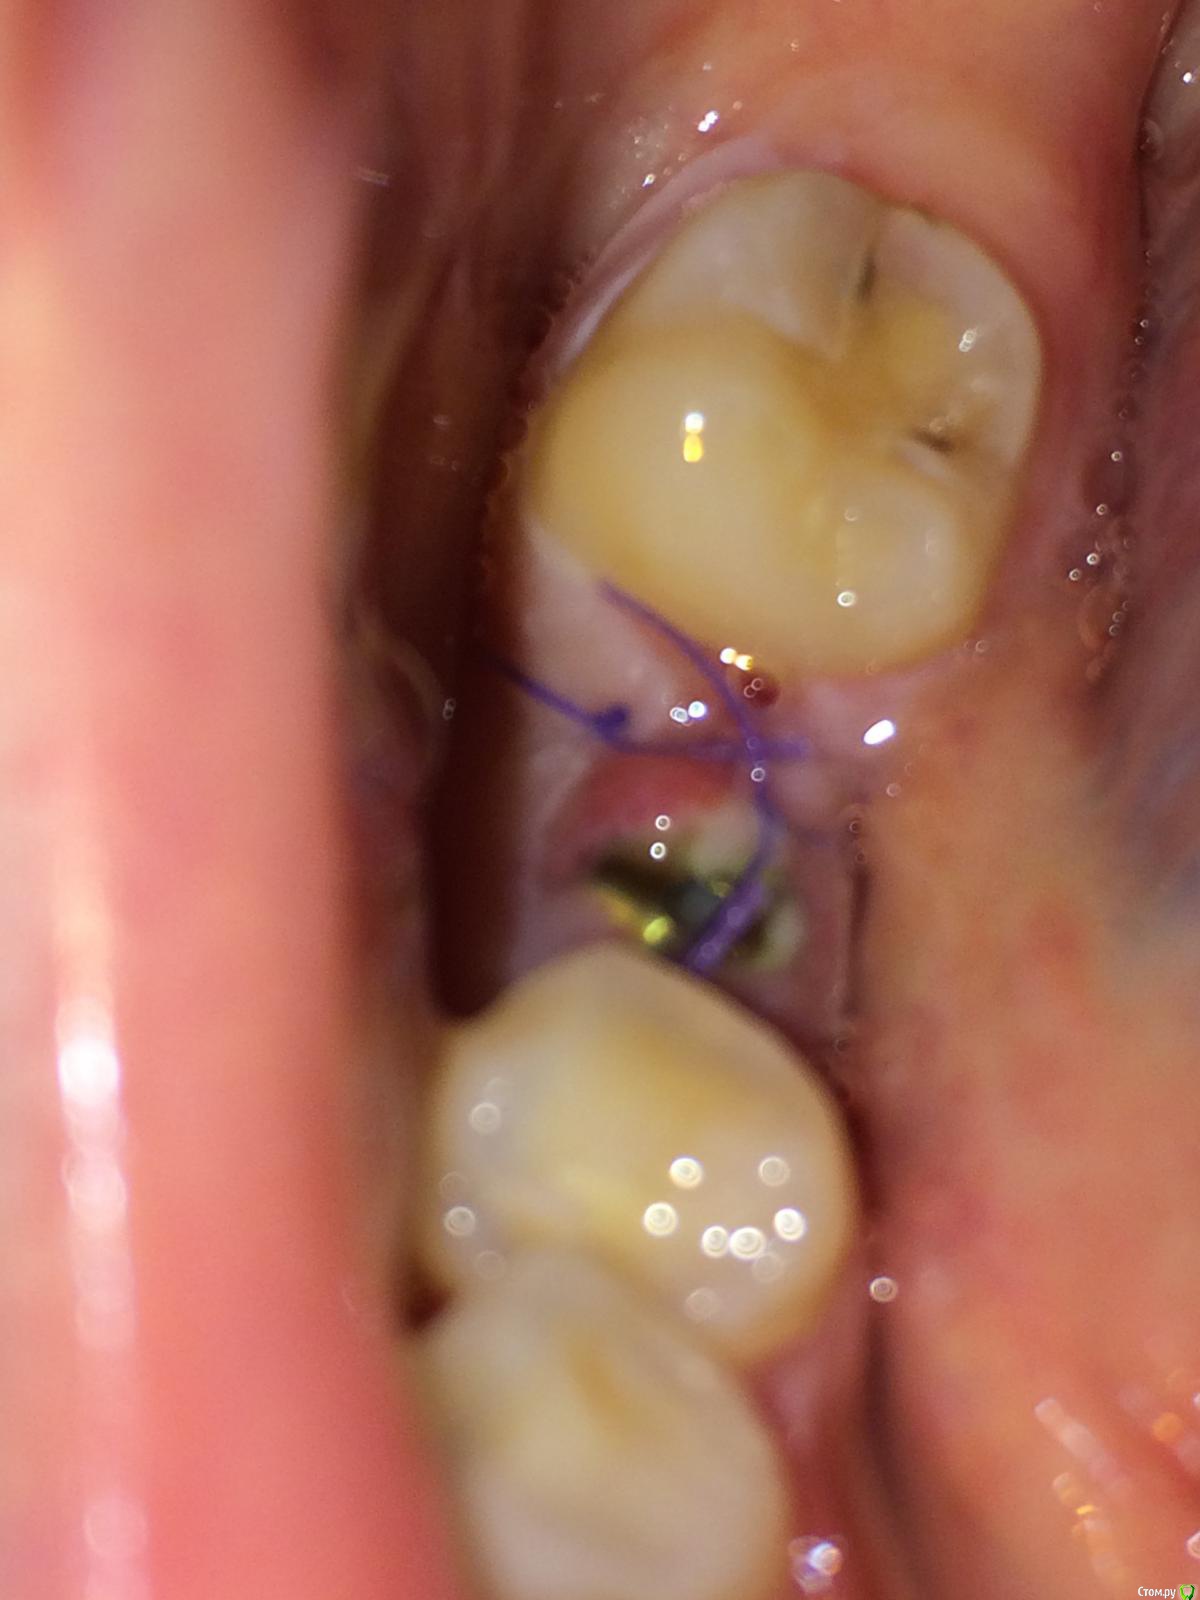

flyfli Опубликовано 20 октября, 2017 Поделиться Опубликовано 20 октября, 2017 (изменено) Уважаемые доктора,помогите ,пожалуйста, очень переживаю,сегодня 5 ый день после имплантации и возле формирователя немного красновато и припухло с одной стороны, боли нет,но очень страшно,все ли впорядке как вы думаете? Такое может быть покраснение нормой? Изменено 20 октября, 2017 пользователем flyfli Ссылка на комментарий

flyfli Опубликовано 20 октября, 2017 Автор Поделиться Опубликовано 20 октября, 2017 там формирователь, вот попробовала поближе там обвела кружком подозрительное место Ссылка на комментарий

red_butler Опубликовано 20 октября, 2017 Поделиться Опубликовано 20 октября, 2017 там формирователь, вот попробовала поближе там обвела кружком подозрительное местотогда ничего страшного, антисептическая обработка и ждать Ссылка на комментарий